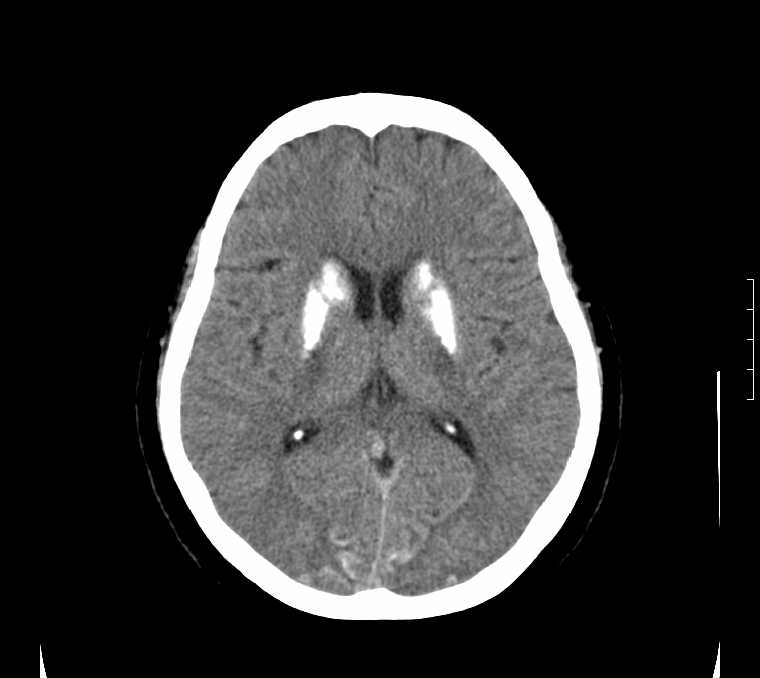

标题: CT24387:看看这例脑部改变!!

老年女性。头晕。

考虑:甲旁减。

fahr病

鉴别于特发性家族性脑血管亚铁钙沉着症(fahr`s病)与甲状旁腺机能低下之间,请结合临床及相关实验室检查。